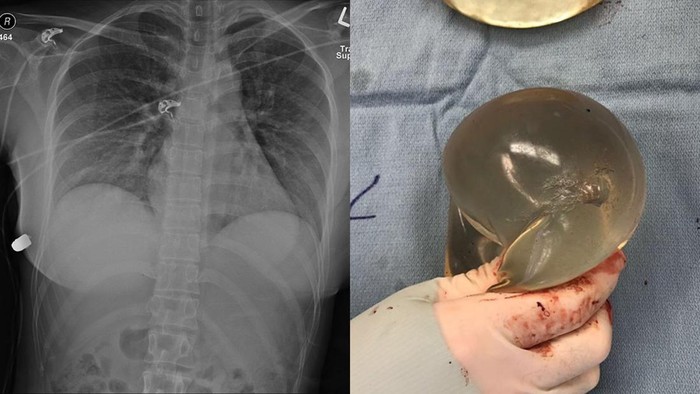

Dikutip dari laman Sage Journals, wanita tersebut berusia 30 tahun dan memiliki implan payudara berukuran 450 mL. Ia mengalami penembakan saat sedang menyusuri jalan, kemudian merasakan panas dan nyeri di bagian dada kiri. Ia sempat mengecek payudaranya dan melihat ada darah. Ia segera membawa diri ke UGD setempat.

“Pasien dipindahkan ke pusat trauma kami dalam kondisi stabil tanpa cedera tambahan. Pemeriksaan klinis mengungkapkan pasien yang nyaman tanpa tekanan dengan luka masuk tunggal di bagian superior payudara kiri,” tertera dalam laman Sage Journals, dikutip detikcom, Sabtu (25/2/2023).

“Luka masuk menunjukkan cedera termal di sekitar lubang peluru yang menunjukkan jarak yang dekat dengan senjata api yang sedang keluar. Massa keras, subkutan, seperti peluru juga teraba di dinding toraks anterior kanan bawah inferior payudara kanan,” sambungnya.

Melalui pembedahan, dokter melepas implan payudara kiri wanita tersebut. Setelah diperiksa, dokter menemukan saluran peluru mulai tepat di bawah luka masuk hingga di payudara kanan. Peluru yang ditemukan dokter kemudian diserahkan ke pihak polisi untuk keperluan forensik.